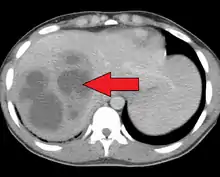

Liver abscess on axial CT image: a hypodense lesion in the liver with peripherally enhancement.